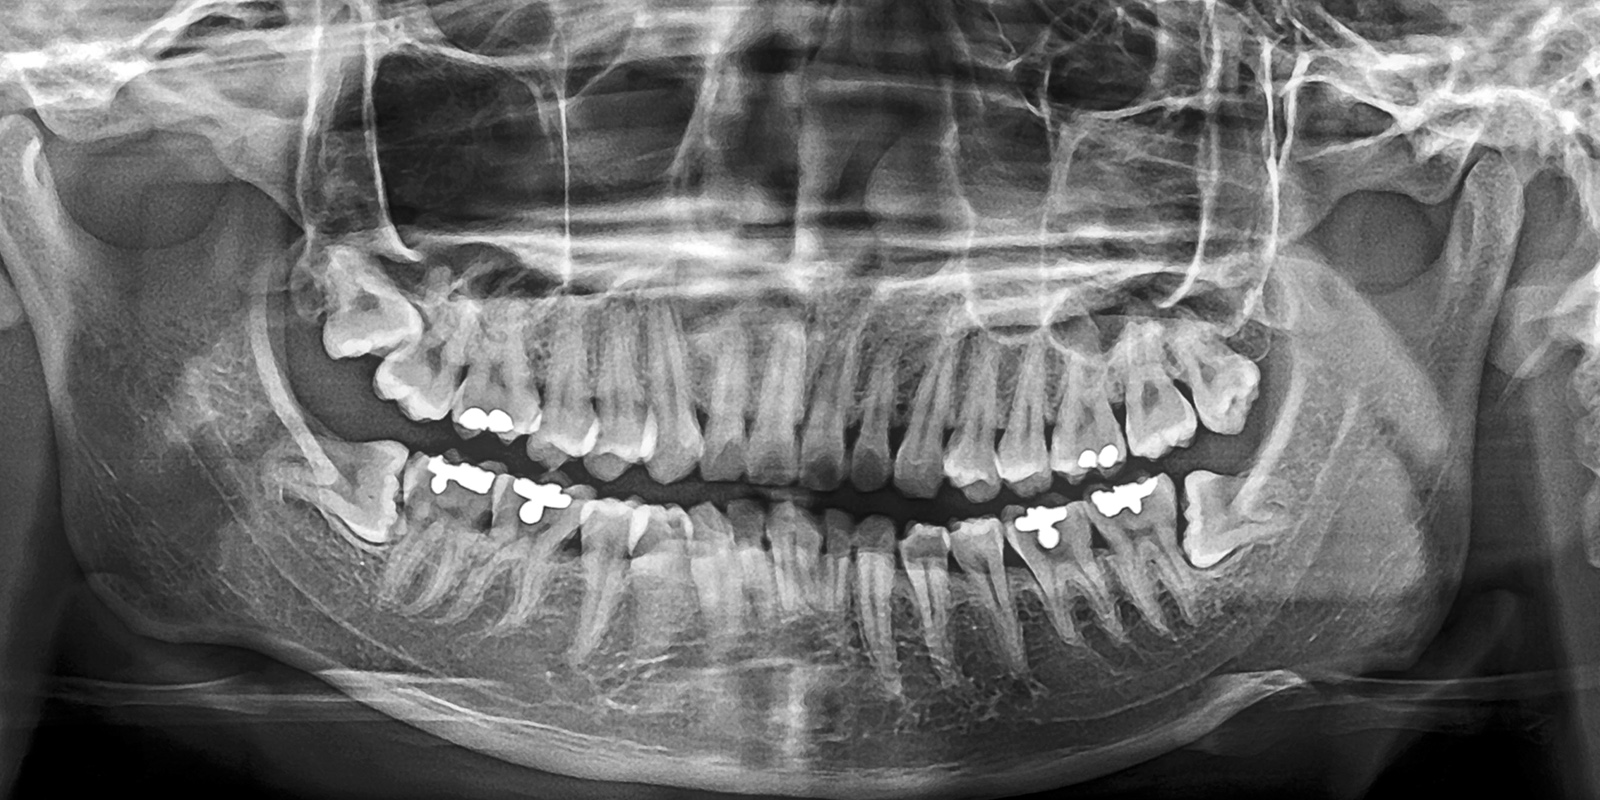

パノラマレントゲン

パノラマレントゲンは、お口全体を1枚の画像で撮影できる広範囲のレントゲン技術です。これにより、親知らずの位置や向き、周囲の歯との関係が一目で把握できます。

特に下あごの親知らずについては、下歯槽神経という重要な神経の近くに位置することが多いため、抜歯による神経損傷のリスク評価が非常に重要です。このパノラマ撮影を用いることで、神経との距離や重なり具合を事前に確認することが可能です。